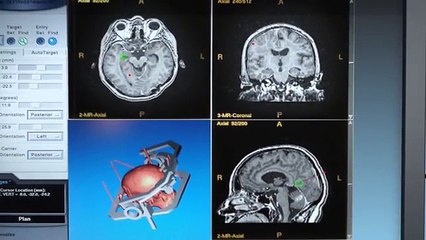

Елена Малышева: Аневризма сосудов головного мозга

В этом выпуске программы "Жить здорово" Елена Малышева со своими медицинскими коллегами расскажет полезную информацию.